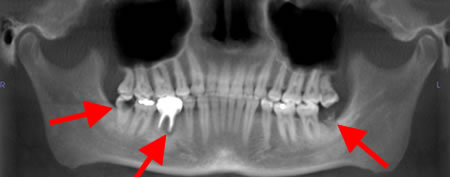

Panoramic radiograph showing decayed bilateral mandibular third molars and failed root canal treatment with periapical lesion related to the right mandibular first molar (middle arrow); also shows carious bilateral mandibular third molars on both sides

From the personal collection of Melanie S. Lang and Thomas B. Dodson